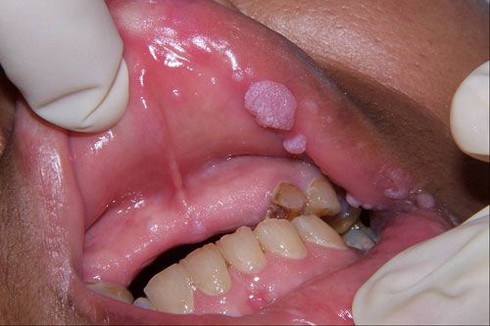

![]() |

Biểu hiện bệnh sùi mào gà ở miệng (ảnh: internet) |